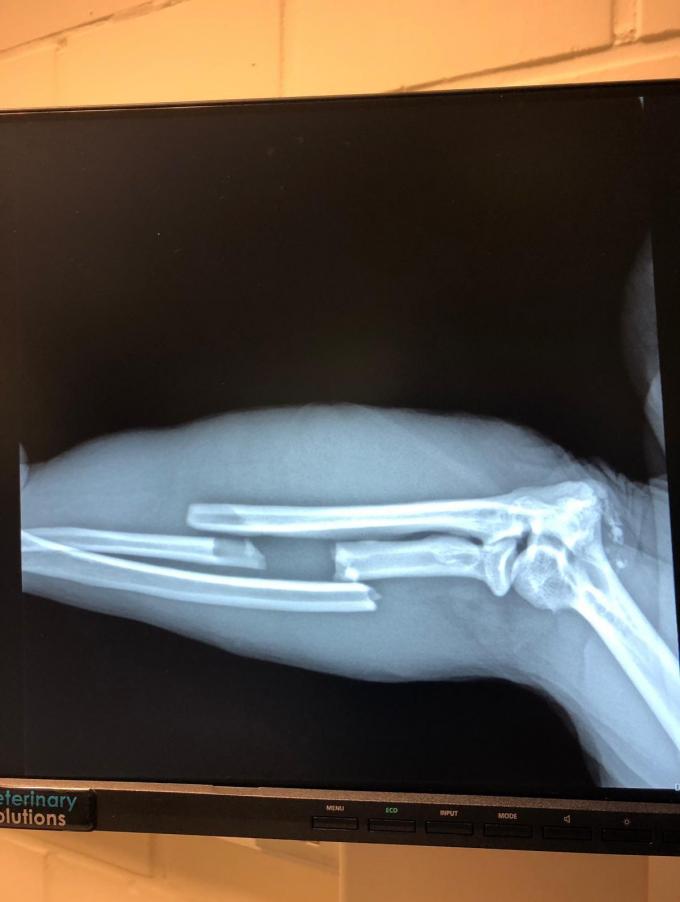

Gebroken arm

Aziza is één van de berberapen die een nieuwe thuis vond in De Zonnegloed. Ze werd gevonden nadat een eigenaar in Duitsland haar had achtergelaten. Aziza werd in 2013 opgevangen door Stichting AAP om daar te worden samengevoegd met soortgenoten. Ze vond in De Zonnegloed een permanente woonplaats. “We merkten dat Aziza haar arm dicht bij haar lichaam hield. Dieren proberen het vaak te verbergen als ze pijn hebben en ook bij Aziza was dat zo. Op de RX-foto’s was een flinke breuk te zien. Wanneer of hoe Aziza precies haar arm brak, weten we niet. Ondertussen heeft ze een gips gekregen, zodat haar arm goed kan herstellen.